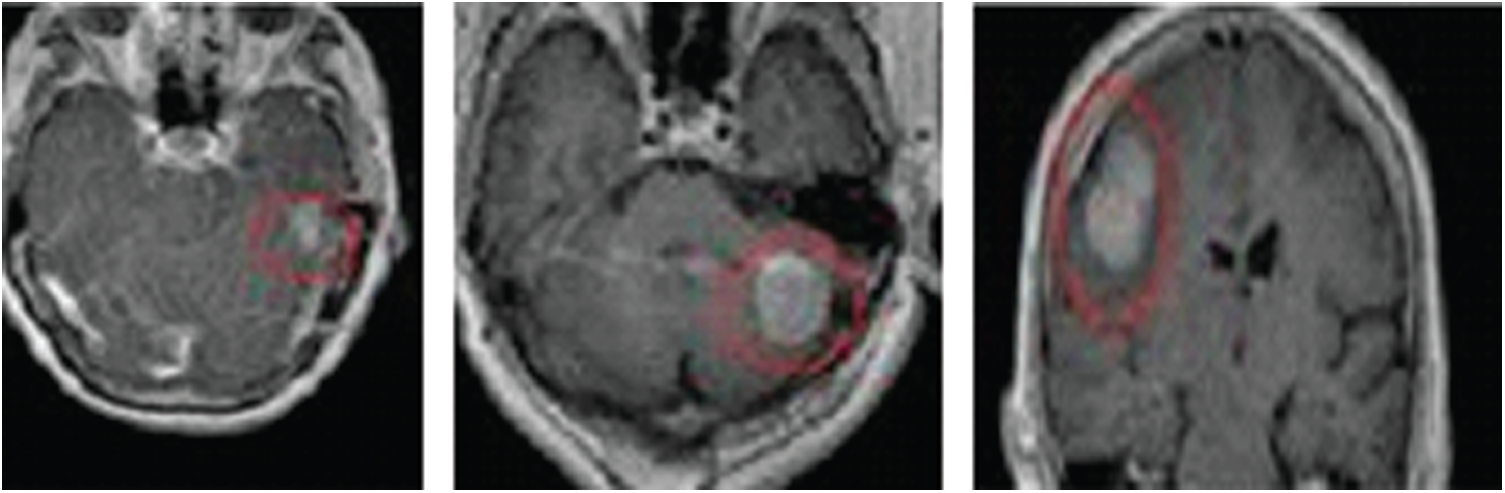

Figure 2: MRI images showing astrocytoma brain tumor in AC–PC and sagittal planes. The tumor is outlined with a pink mark

MRI images for real patients with and without tumors were taken from the database in [11]. The dataset we used included 680 MRI images of astrocytoma tumors, 520 MRI images of gliomatosis cerebri tumors, and 700 MRI images of glioblastoma tumors. Another 680 MRI images of normal-cell brains without tumors are also included in our dataset. All images are captured in the sagittal plane and the anterior commissure–posterior commissure (AC–PC) plane, which is an axial MRI plane that is widely used. Fig. 2 presents an example of MRI images showing a brain tumor in the AC–PC and sagittal planes.

Instances of tumors classified from the used dataset via 10-fold cross-validation testing are displayed in Fig. 5. (The tumors are marked in pink outlines.)

Figure 5: Instances of classified tumors from the used dataset using 10-fold cross-validation testing